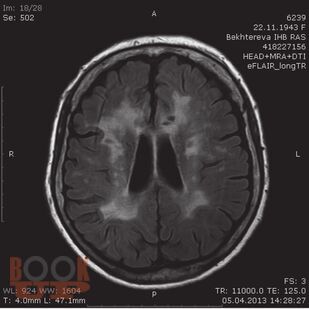

Настоящая брошюра, посвященная многозначному представлению о дисциркуляторной энцефалопатии, расшифровывает эту формулировку и позволяет более точно и осознанно оценивать подобных больных, а значит, и проводить им адекватное лечение. Наиболее детально здесь рассматривается атеросклероз мозговых артерий с его признаками на магнитно-резонансных и позитронно-эмиссионных томограммах, а также анализируется характерный для этой патологии липидный состав крови.